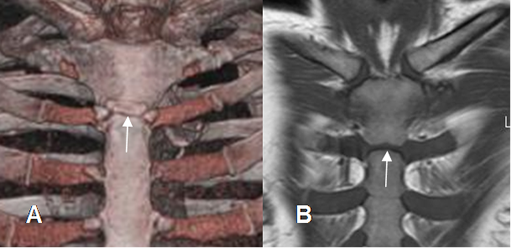

Fig 4. Angulo de Louis.

A: TAC reconstrucción coronal y B: RM coronal en T1. Articulación entre el manubrio y el cuerpo esternal a nivel de la 2ª articulación condrocostal, que forman en ángulo de Louis.